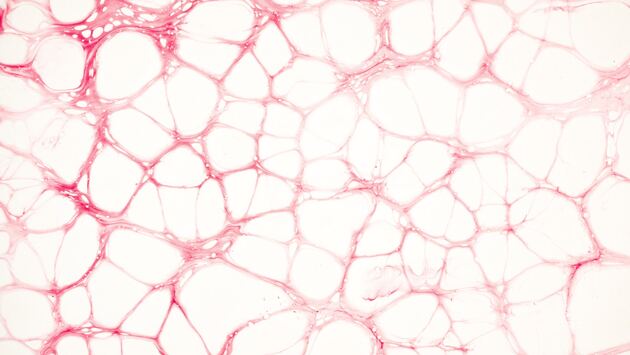

Атеросклеротические бляшки – опасные признаки атеросклероза. Таким термином называют отложения холестерина, из-за которых сужаются артерии.

Холестириновые отложения в сосудах формируются по двум причинам. Первая — генетическая предрасположенность, вторая — внешние факторы:

Также атеросклероз может развиваться на фоне сахарного диабета, метаболического синдрома и вследствие эндотелиальной дисфункции, которая развивается по целому ряду причин.

Но при всем этом всегда причиной развития атеросклероза будет являться эндотелиальная дисфункция. То есть до определенного момента в норме наши здоровые сосуды могут препятствовать росту атеросклеротической бляшки, но когда поражений эндотелия становится много, этот механизм нарушается.